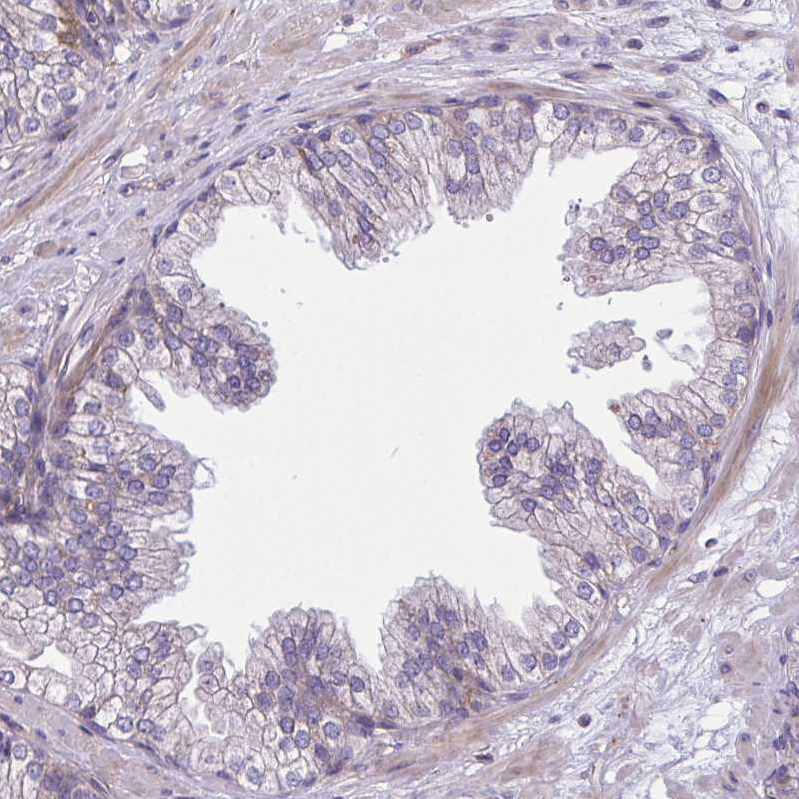

Immunohistochemical staining of human kidney shows strong cytoplasmic positivity in cells in tubules.